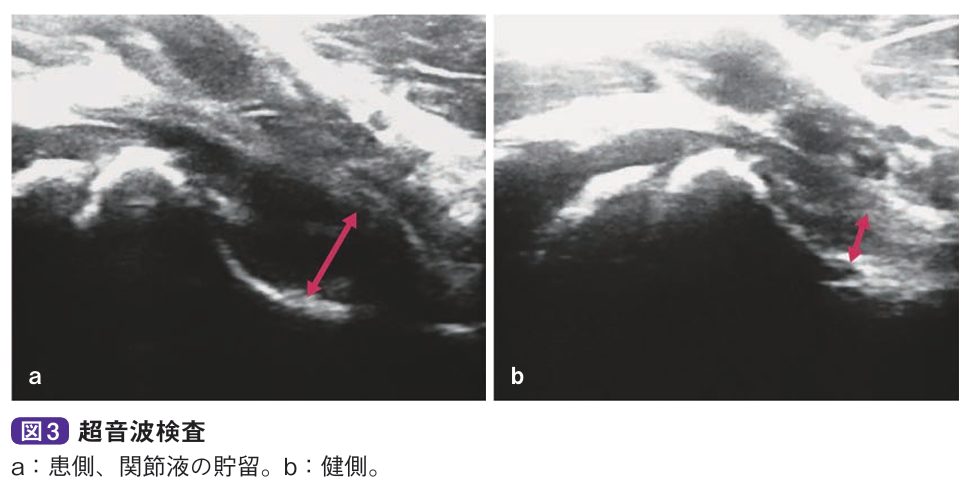

診察とレントゲン、エコーなどで診断します。関節可動域は軽-中等度と制限され、とくに屈曲位で内旋が制限されます。微熱を認めることがありますが、通常、血液所見は正常値を示します。単純X線像では関節液の貯留により関節包陰影の膨隆、関節裂隙(れつげき)の開大、骨頭の外方化などを認めますが、骨陰影に異常を認めません。超音波検査やMRI検査で関節液貯留が明らかとなります。